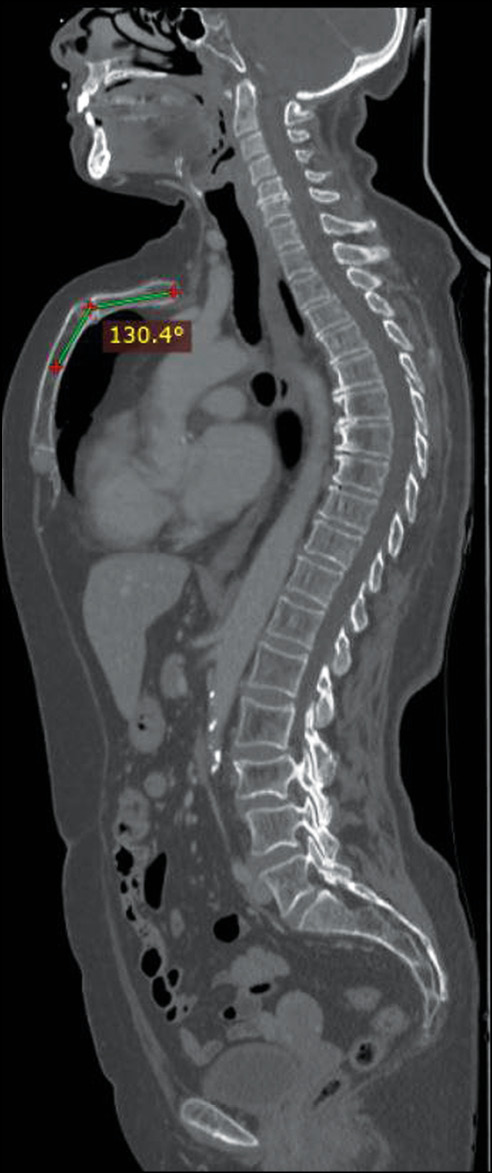

Fig 1. Sagittal whole body computed tomography scan showing an arching sternum and a chondromanubrial deformity with a dorsal-open angle of 130°.

Fig 4. Computed tomography reconstruction of the rib cage showing that the sternum has a normal length and is not depressed in the lower third.